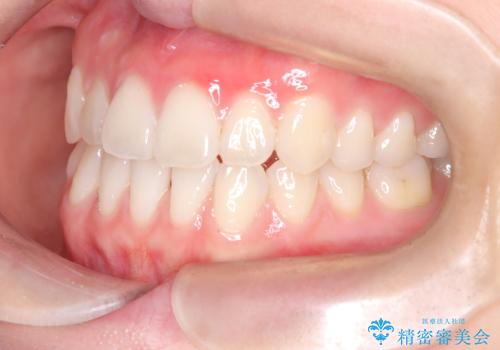

八重歯と前歯の逆の咬み合わせを、目立たない矯正で同時に改善

- 八重歯と、右上前歯(2番)が下の歯より内側に入っている反対咬合を気にされてご来院されました。精密な検査の結果、八重歯と反対咬合を同時に改善するためには、歯列全体にスペースを確保する必要があると判明。患者様のご希望から、透明で目立たないインビザライン(マウスピース矯正)による治療計画を立案しました。奥歯全体を奥へ動かす遠心移動でスペースを作り、これらの複雑な問題を一括で解消することを目指します。

今回の矯正治療では、透明なマウスピース型の装置インビザラインを使用しました。治療は、緻密なデジタル計画に基づき、奥歯から順に歯列全体を後方へ移動させる遠心移動を実施。これにより、八重歯を正しい位置に並べるためのスペースを確保しました。同時に、右上の2番を前方に誘導することで反対咬合を解消。結果として、抜歯することなく八重歯と反対咬合という複数の問題が改善され、機能的で美しい歯並びを獲得していただけました。